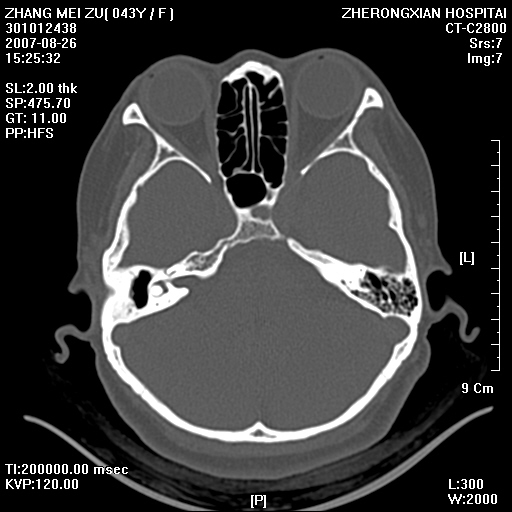

标题: CT9512:F43Y,是肉芽肿还是胆脂瘤?诊断报告该如何出? [打印本页]

标题: CT9512:F43Y,是肉芽肿还是胆脂瘤?诊断报告该如何出?

右耳硬化性乳突炎并鼓窦入口胆脂瘤形成,左侧乳突炎

右侧中耳乳突炎,伴鼓窦入口胆脂瘤形成.

右耳硬化性乳突炎并鼓窦入口胆脂瘤形成,左侧乳突炎.

右侧慢性中耳乳突炎伴胆质瘤形成.左侧乳突炎.

支持右侧中耳乳突炎伴鼓窦入口处胆脂瘤。

典型胆脂瘤,从上鼓室,乳突窦入口到乳突窦有明显光滑的骨质破坏和软组织结节均为胆脂瘤特点.而肉芽肿对骨质的破坏是轻微的.值得关注的是乳突后壁被破坏只剩薄薄的一层,如果再不尽快治疗,胆脂瘤如果突破其后壁即可能形成耳源性脑脓肿了.